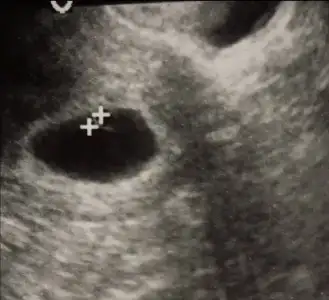

Ne zaman 15 mm olur dedi peki canım sanaYok canım. Benim kese 5 mm daha. 15 mm de görülüyormuş bebiş:) biraz daha bekliycem onun için.

Baksana artıların oldu yer bebek ya kesenın ıcınde yukarda dıye dedımEvde cnm buyutsene gotoyu

Oyy ya inanmıyorum ne zaman gözüktü canım burdaBaksana artıların oldu yer bebek ya kesenın ıcınde yukarda dıye dedım

Pazartesı 6+1 de alttan gozuktu kalp atısıda bar duzenlı dedı dr cnmOyy ya inanmıyorum ne zaman gözüktü canım burda

Karından gizukmezmi acabaPazartesı 6+1 de alttan gozuktu kalp atısıda bar duzenlı dedı dr cnm